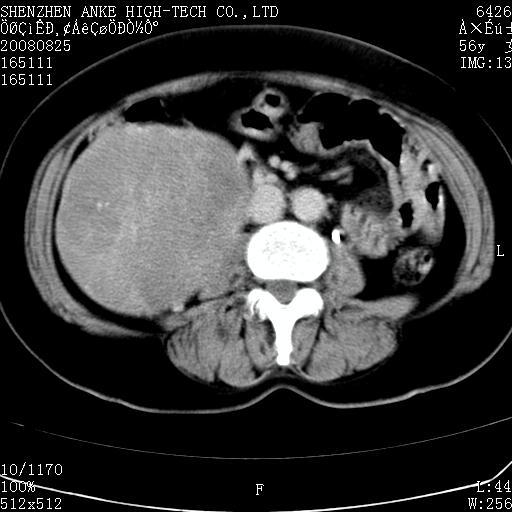

患者,女性,56岁,腰痛3年,查:右腹部约8x10cm肿块,固定,无压痛;8月23日在外院做了平扫,发现右肾巨大肿块(外院具体诊断不祥);今天在我院做了静脉肾盂造影,示:右肾明显增大,分泌功能明显减弱。

1)考虑右肾癌并右肾静脉瘤栓形成。2)脂肪肝。